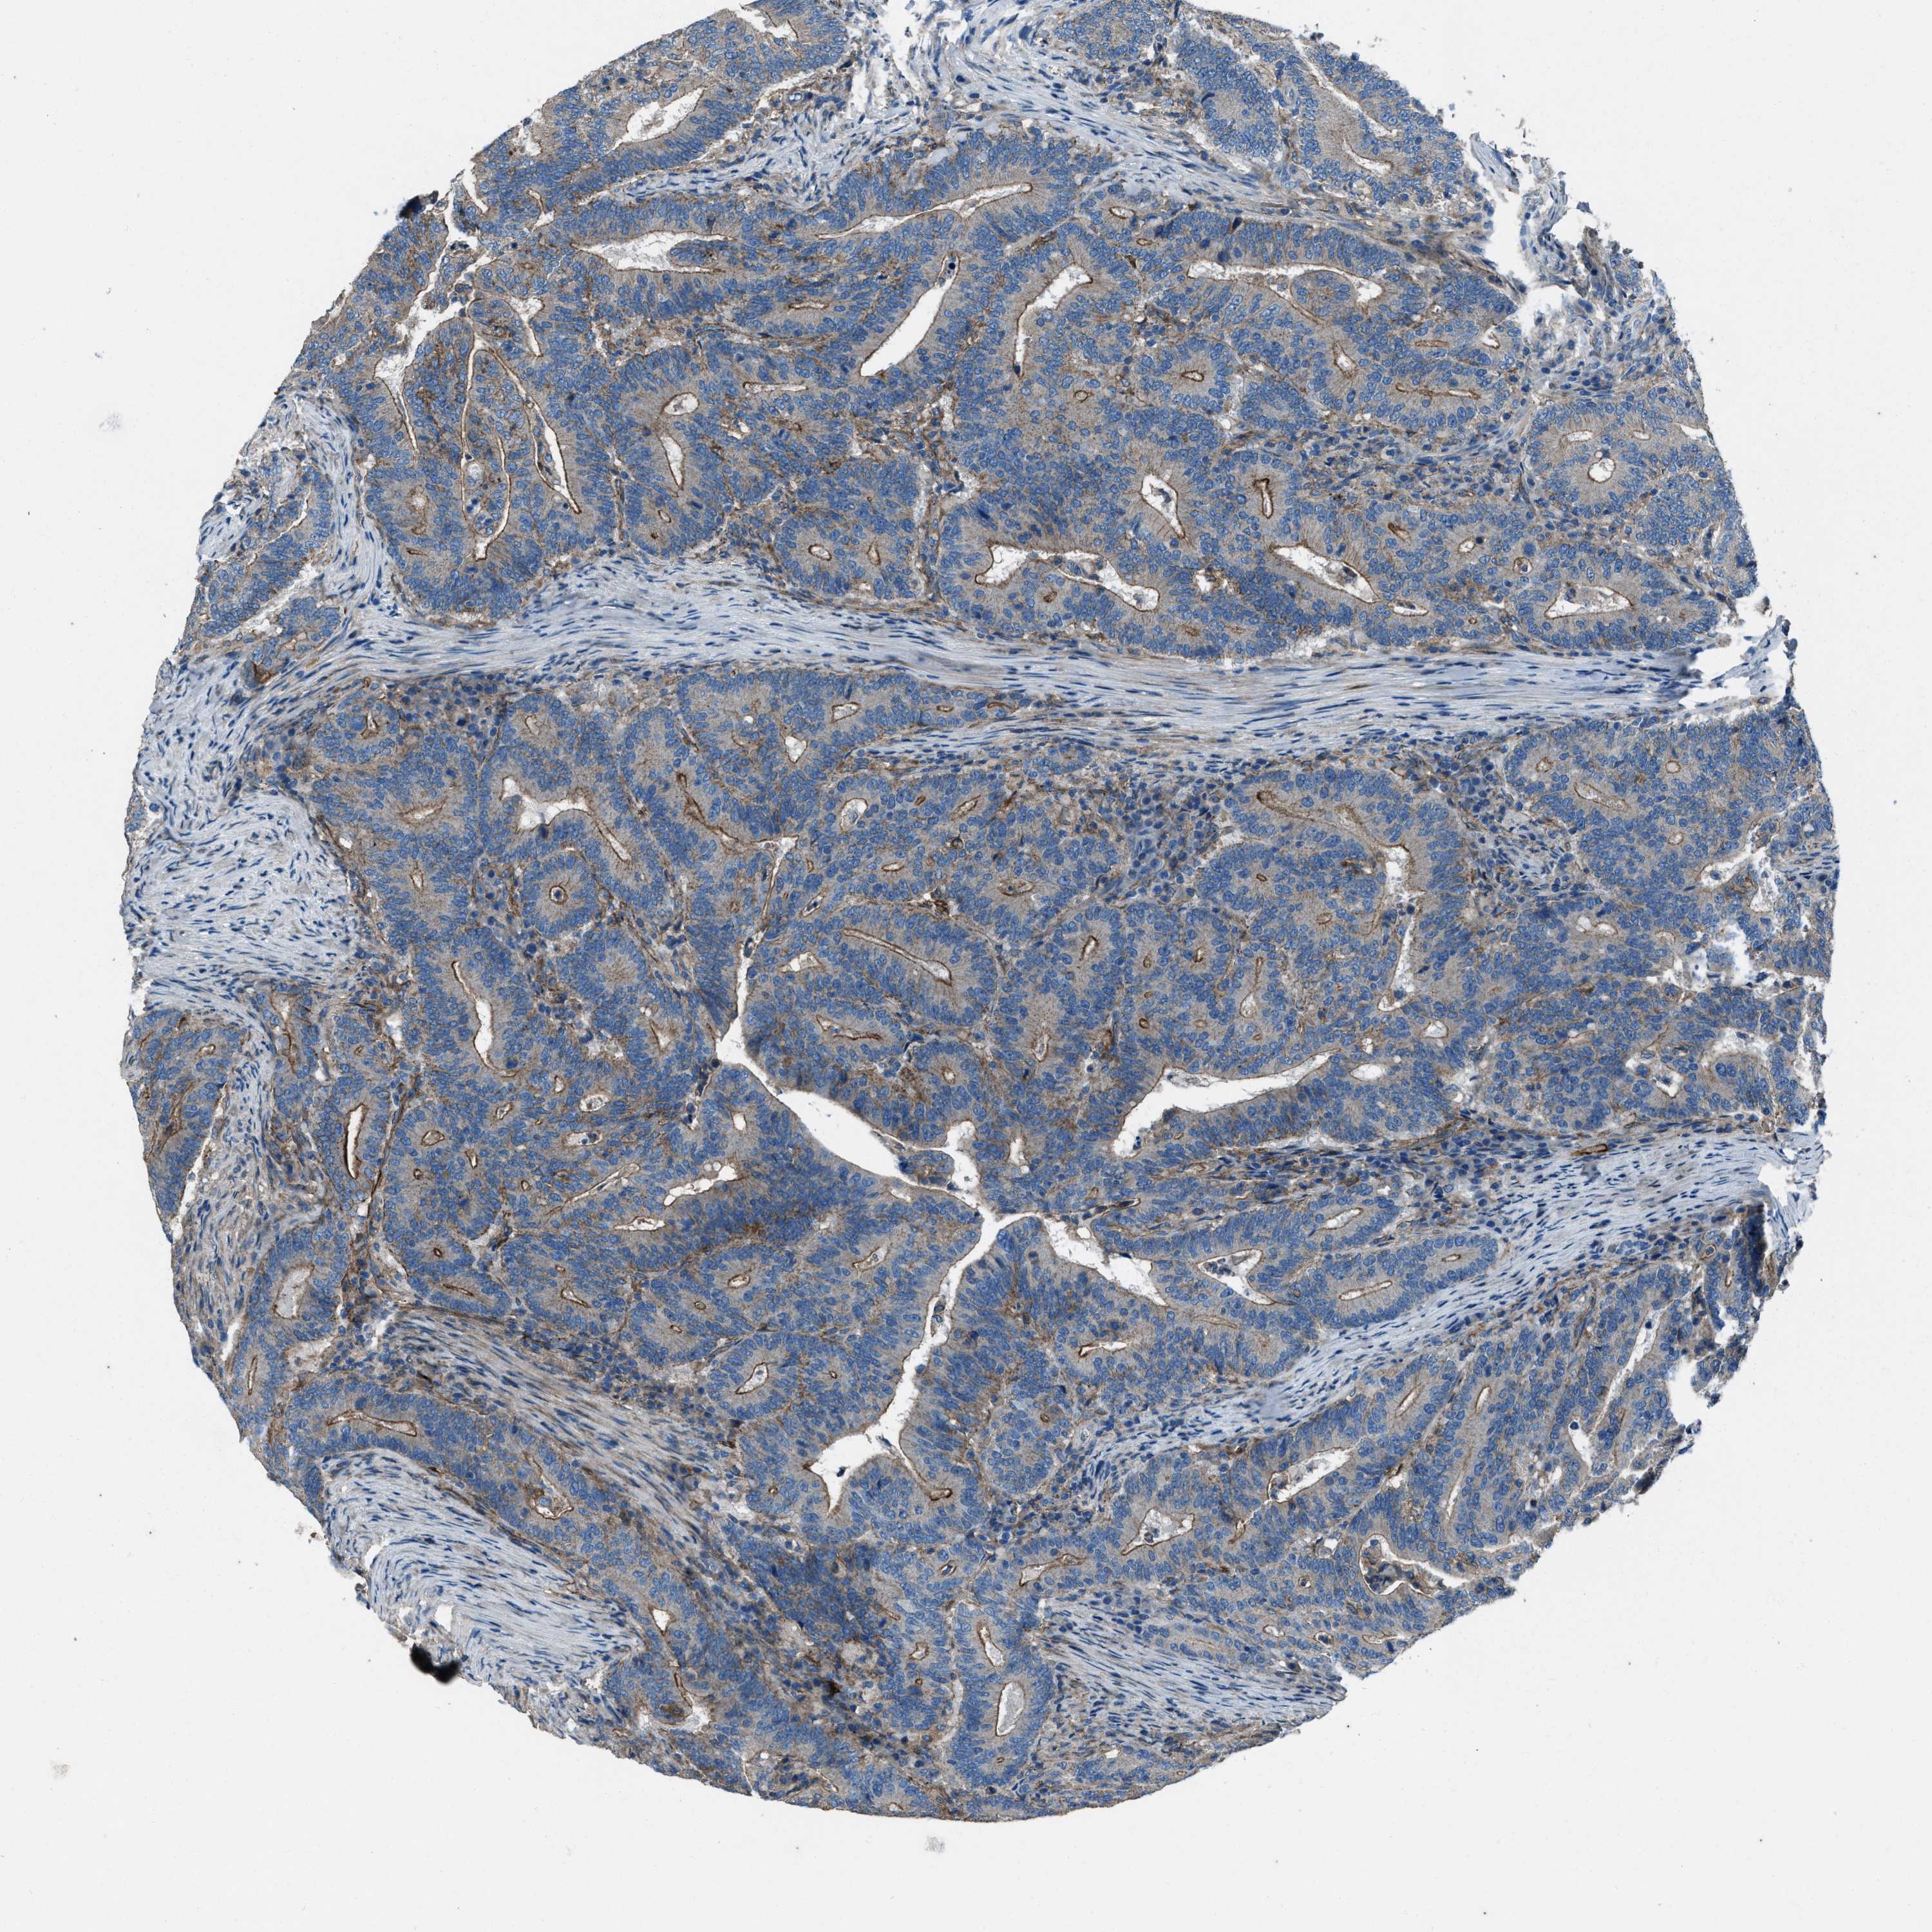

CANCER COLORECTAL CANCER Show tissue menu

COAD TCGA COAD VALIDATION READ TCGA READ VALIDATION PROTEIN COAD CPTAC PROTEIN EXPRESSION

ANTIBODIES

AND

VALIDATION